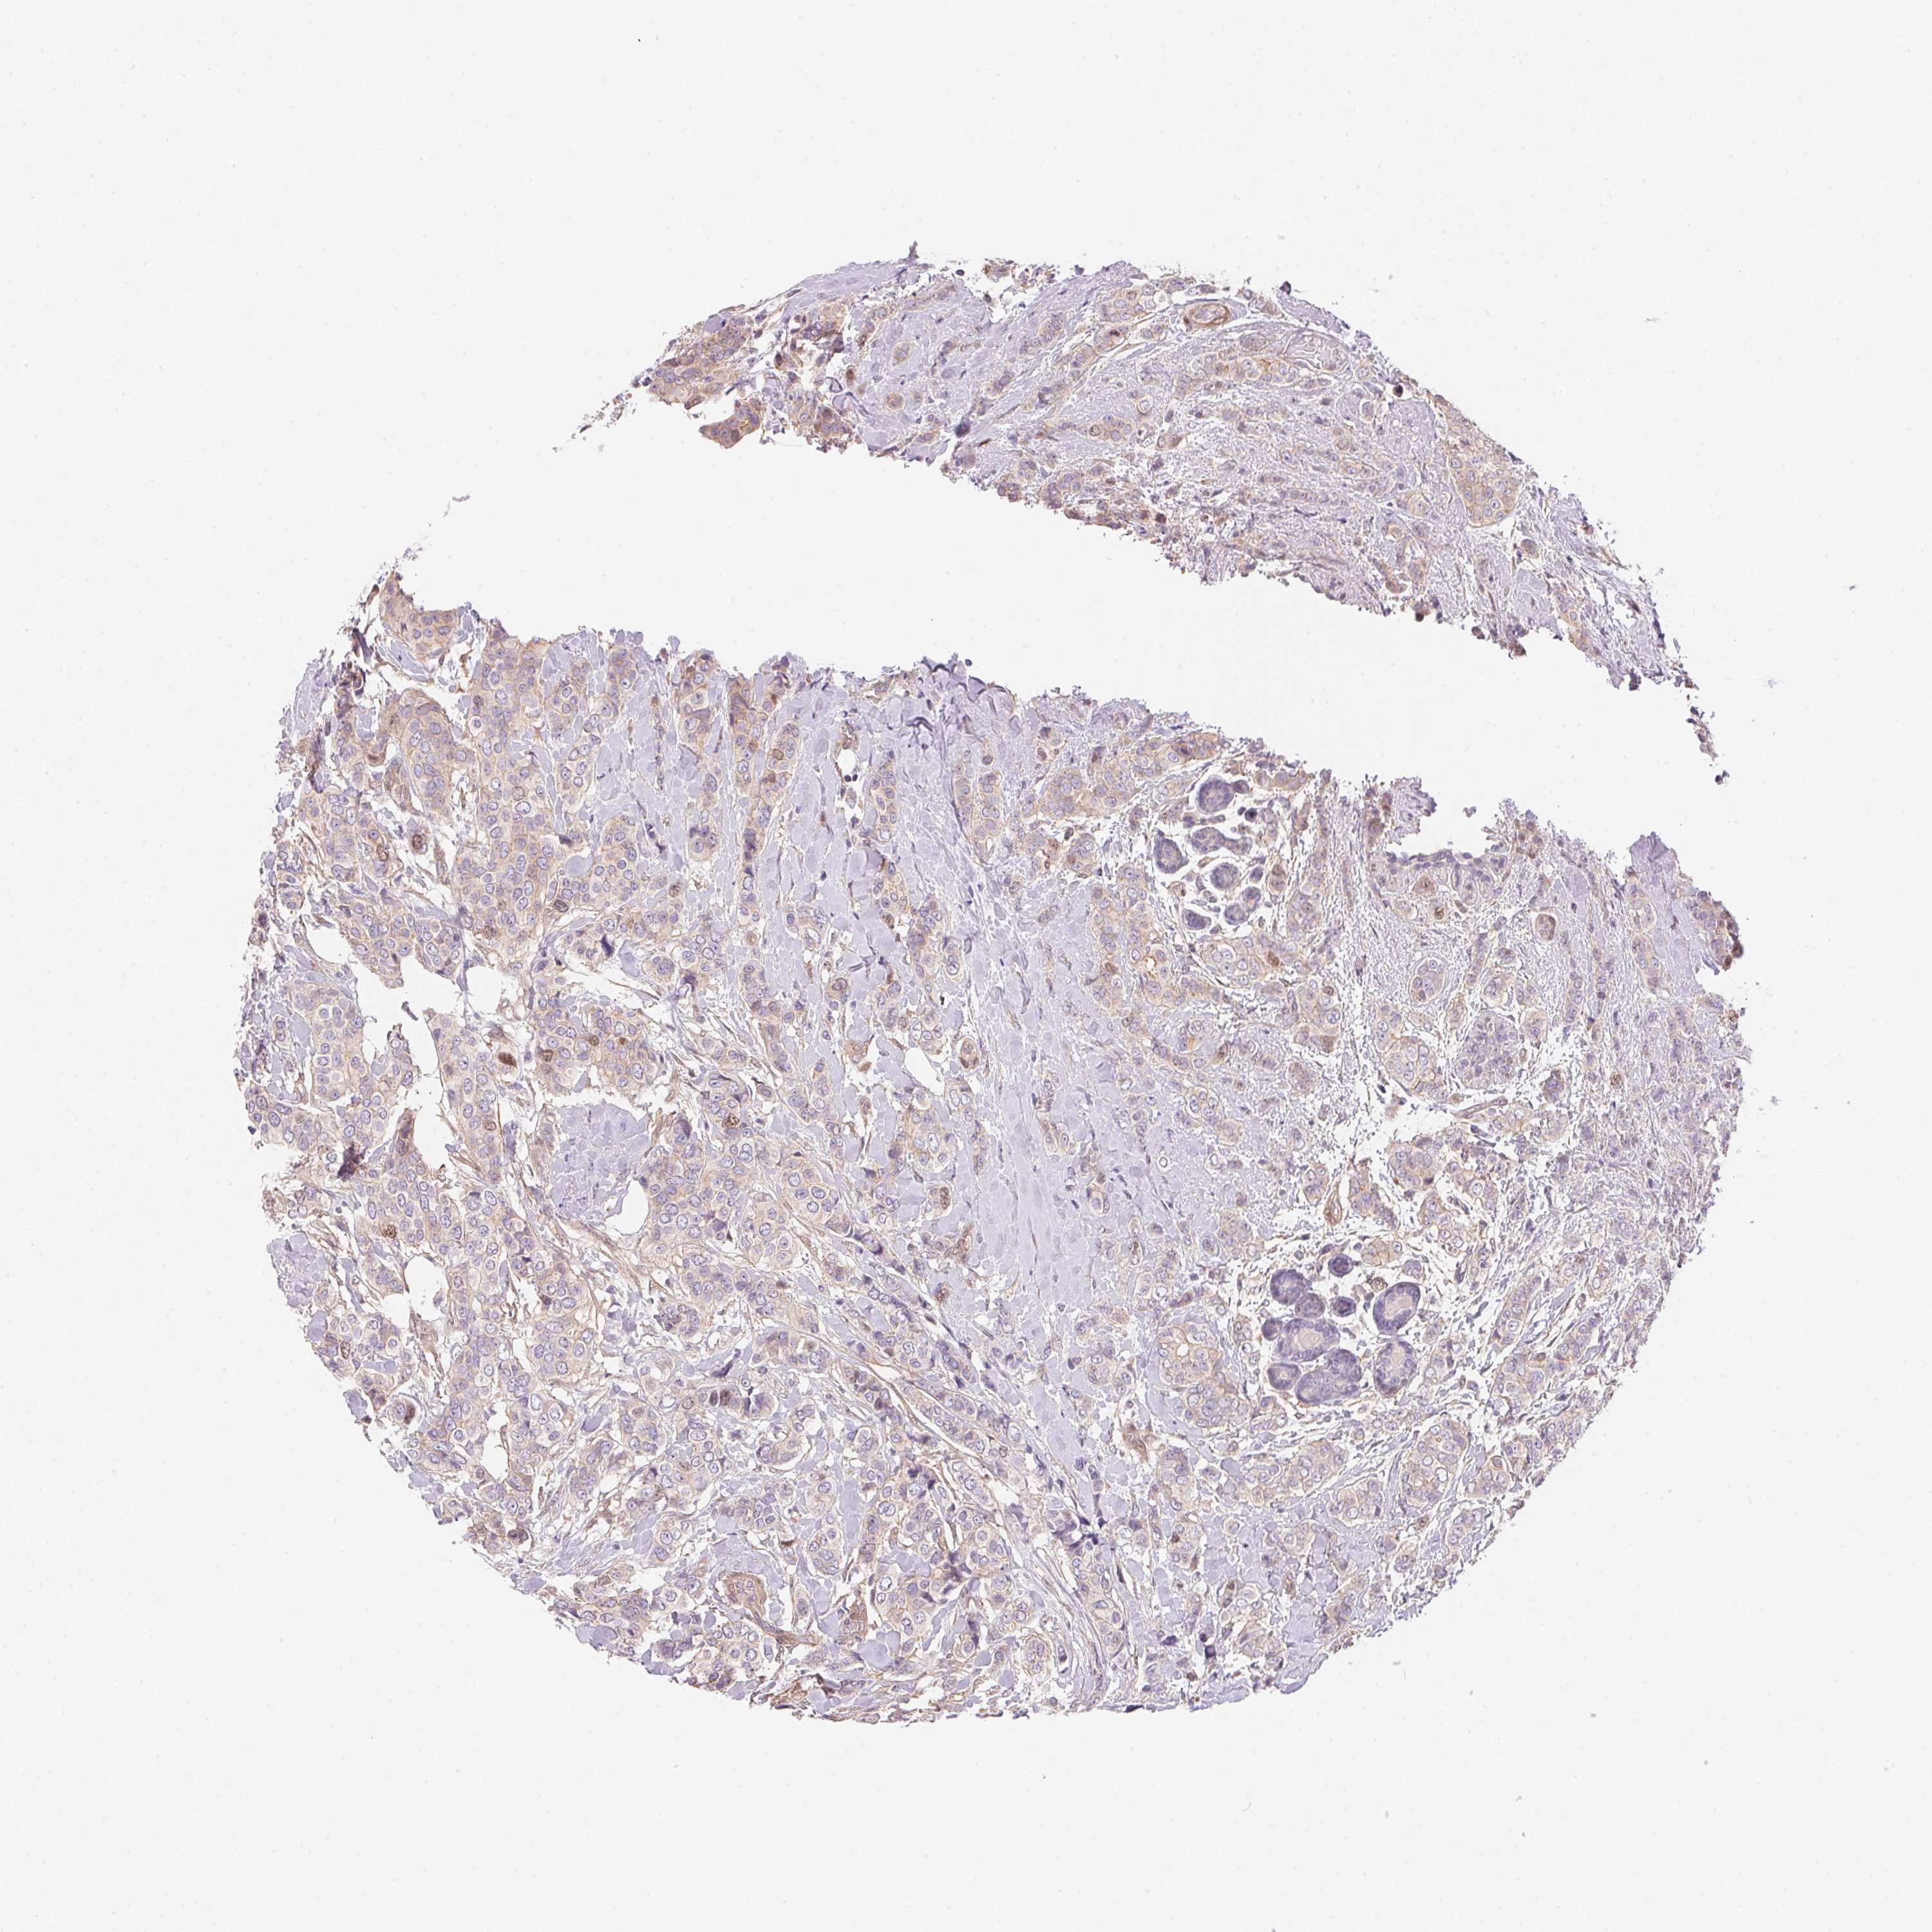

CANCER BREAST CANCER Show tissue menu

BRCA TCGA BRCA VALIDATION PROTEIN EXPRESSION